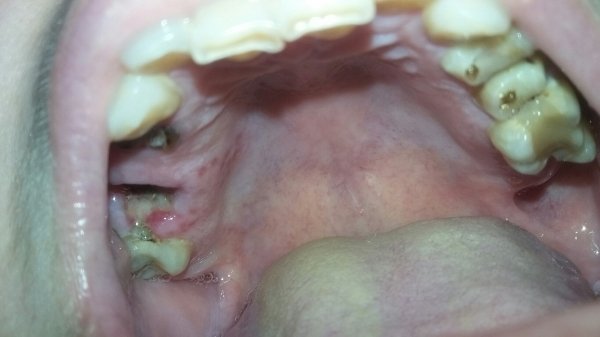

В десне в самом низу появились два твердых шарика, они не двигаются. Если провести пальцем по десне между щекой и десной, то они ощущаются, но дискомфорта нет. 2 года назад в этом месте мне удалили зуб (нижний 6), иногда десна воспаляется после холодного и опухает, появляется гной.

Вам необходимо проделать рентген снимки и определить причину воспалений и экссудата. Уплотнения, как и воспаление, могут быть связаны с остатками корней после удаления. Обратитесь на прием к врачу, и все разрешится.